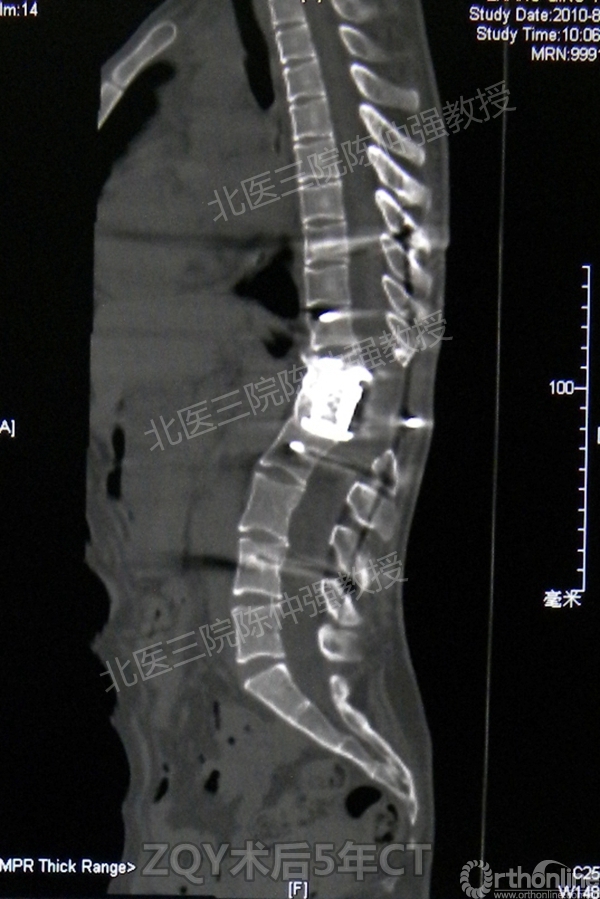

ZQY术后5年

患者女性17岁,胸腰椎陈旧结核性侧后凸畸形,局部呈“麻花状”扭转,无神经功能受损表现。2005年,陈仲强教授带领团队实施后路+侧前方联合入路脊柱节段切除、双轴旋转矫形术。术后患者外观显著改善,神经功能正常。术后随访证实患者截骨矫形节段骨性融合良好,矫形效果持续良好。